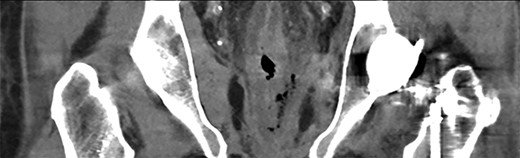

In retrospect, the patient reported anal pain during administration of a fleet enema 3 days prior. On inspection of the anus, there was a necrotic area leading into the anal canal. This finding of perianal trauma associated with the increasing evidence of sepsis led to a presumptive diagnosis of FG. CT scan (Fig. 2) demonstrated an area of hazing and small amounts of free gas within the perirectal tissue suggestive of a rectal perforation or FG. The patient was taken to theatre for an urgent intervention. The scrotum and perianal region required debridement of the affected soft tissue (Fig. 1). Sigmoidoscopy demonstrated circumferential necrosis of the lower portion of the rectum consistent with REI (Fig. 3). A decision was made to expectantly manage the rectal injury and perform a repeat sigmoidoscopy with the aim of preserving the rectum in lieu of an urgent rectal resection. The antibiotic regime was changed to meropenem, clindamycin and vancomycin. Tissue cultures from the debridement grew scant colonies of Pseudomonas aeruginosa and Bacteroides uniformis. The repeat sigmoidoscopy demonstrated stabilization of the rectal ischaemia. A diverting colostomy was created to assist in application and management of negative pressure dressings to the perineal wound (Fig. 4). He required 2 days of post-operative ICU support and over the next 2 weeks, symptoms and inflammatory markers returned to normal. An examination under anaesthesia performed 1 week later demonstrated interval improvement of the rectal mucosa with resolving necrosis. The patient was discharged after 3 weeks with no further dressings and the colostomy was reversed 3 months later.

Operative photo. Extent of debrided soft tissue at time of initial intervention.